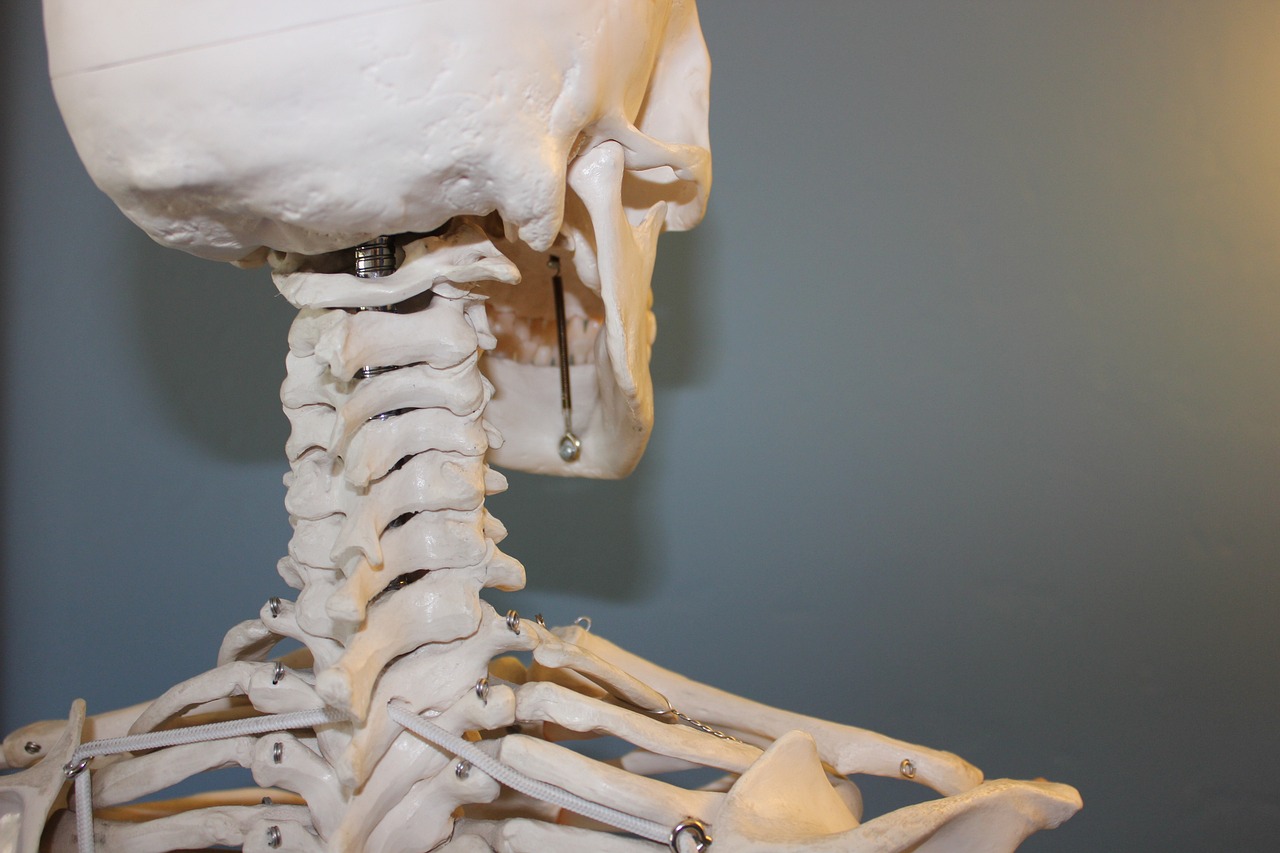

관절 건강은 나이가 들수록 신경 써야 할 중요한 건강 요소입니다. 관절은 신체의 움직임을 가능하게 하는 역할을 하며, 이를 지키기 위해서는 올바른 식습관, 적절한 운동, 그리고 필요한 영양제를 섭취하는 것이 중요합니다. 아래에서는 관절 건강을 유지하고 개선하는 데 도움을 줄 수 있는 방법들을 소개합니다.

2. 관절에 좋은 운동

운동은 관절의 유연성과 강도를 유지하는 데 필수적입니다. 그러나 관절에 무리가 가지 않는 운동을 선택하는 것이 중요합니다.